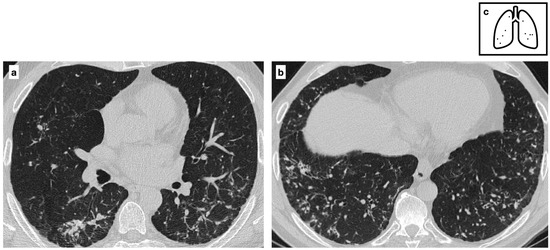

Figure 5.

Patient with previous history of severe varicella pneumonia. HRCT shows bilateral diffuse ill-defined calcified nodules. Scattered diffuse micronodular calcifications are an uncommon late sequela of VZV pneumonia (a,b). Pattern of calcification (c).